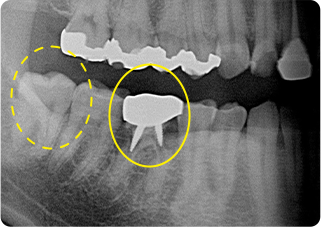

精密根管治療③

術前

術後

| 主訴 | 奥歯で噛むと痛い |

| 治療期間/回数 | 1ヵ月、4回 |

| 価格(税込) | 88,000円(税込) |

| リスク・副作用 | 病変再発、歯根破折の可能性 |

| ポイント | う蝕検知液を用い、むし歯の取り残しが無いようにし、ラバーダム防湿を行い、無菌的に根管治療を行った。根管充填材は、殺菌作用の強い保険適応外のMTAセメントを使用した。 |